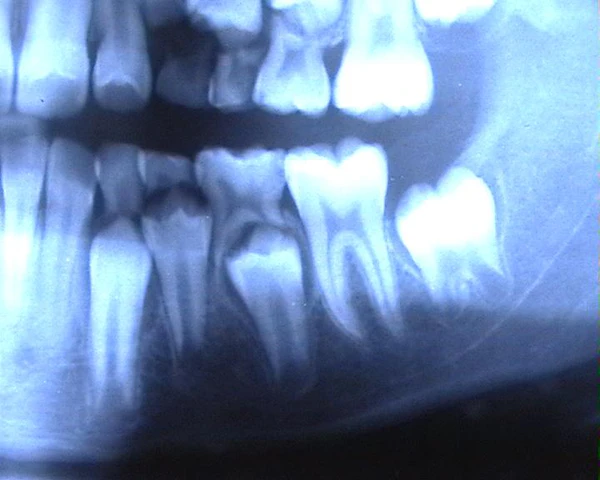

Первый зуб-моховик появляется у ребенка на шестом месяце жизни. К трем годам прорезываются почти все молочные зубы. В шесть лет молочные зубы начинают замещаться первыми постоянными зубами, заканчивается их замена к тринадцати годам. Четыре коренных зуба (зубы мудрости) обычно появляются после 18 лет.

Зачаток постоянного зуба отделен от корня молочного тонкой костной пластинкой. С развитием зачатка постоянного зуба последний начинает давить на костную перегородку. В окружающей соединительной ткани появляются остеокласты, которые и разрушают эту перегородку. Далее процесс начинает идти с двух сторон -- с поверхности корня с помощью остеокластов и со стороны пульпы. Пульпа молочного зуба постепенно превращается в грануляционную ткань, богатую кровеносными сосудами и остеокластами, которая разрушает дентин. Процесс заканчивается полным рассасыванием корней молочных зубов, оставляя одну коронку, которую легко удаляют иногда сами дети или выталкивает растущий постоянный зуб. Прорезывание постоянных зубов не сопровождается какими-либо болезненными изменениями со стороны организма ребенка, как это наблюдается в период прорезывания молочных зубов. Исключение составляют зубы мудрости, которые прорезываются в возрасте от 17 до 25 лет и старше.